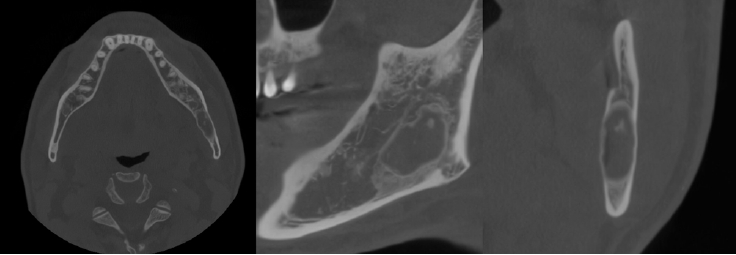

The patient underwent a panoramic radiograph and cone-beam computed tomography (CBCT). The panoramic radiograph showed an ovoid, well-demarcated radiolucency with irregular contour, and internal lytic change beneath the periapical area of the left mandibular third molar region (Fig. 1). CBCT demonstrated a radiolucent lesion with a well-corticated margin and subtle internal calcified foci. Generalized sclerotic changes in the adjacent cancellous bone and thinning of the bucco-lingual cortex were noted, with mild expansion of the lingual cortex due to the lesion (Fig. 2). Anatomically, the lesion lay inferior to the mandibular canal and outside the tooth-bearing alveolus, which argued against an odontogenic origin. Collectively, these features were interpreted as a radiolucent lesion with surrounding sclerosis. Routine laboratory tests (L30 clinical chemistry panel) revealed elevated glucose (135 mg/dL) and total cholesterol (233 mg/dL), while all other parameters were within normal limits. Based on the clinical and radiographic findings-posterior mandibular location, well-defined unilocular radiolucency with a pronounced adjacent sclerotic change, cortical thinning with mild expansion but without periosteal reaction or cortical breach, and non-odontogenic position—the working differential favored non-ossifying fibroma, with a simple bone cyst considered less likely.

Panoramic radiograph shows a radiolucent lesion of irregular shape and relatively well-defined margins beneath the periapical area of the left mandibular third molar.

Axial, parapanoramic, and cross-sectional cone-beam computed tomographic images show a radiolucent lesion with a well-corticated margin and subtle internal calcified foci. Generalized sclerotic changes in the adjacent cancellous bone and thinning of the buccolingual cortex are noted, with mild expansion of the lingual cortex due to the lesion.